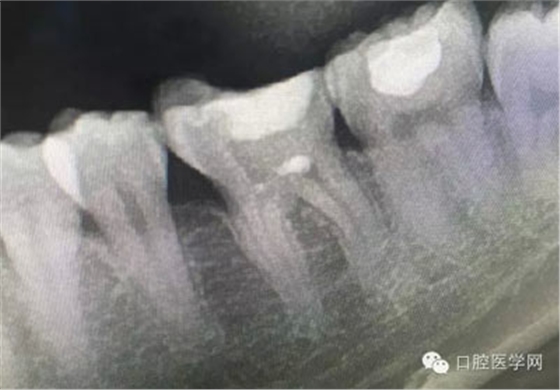

根管再治療是我們比較頭疼的,尤其是那些冠修復(fù)過(guò)的,我們有很多的麻煩需要去溝通,比如可能導(dǎo)致的側(cè)穿、可能沒有看到的腐質(zhì)、可能導(dǎo)致的崩瓷,或者是后期可能出現(xiàn)冠折......這些需要我們和患者好好的溝通。全瓷冠還好些,金屬冠根測(cè)的時(shí)候很是麻煩,總之我們做修復(fù)的時(shí)候不要單純的追求速度,追求效益,適當(dāng)?shù)淖⒁庀挛覀兊幕A(chǔ)治療和設(shè)計(jì)。